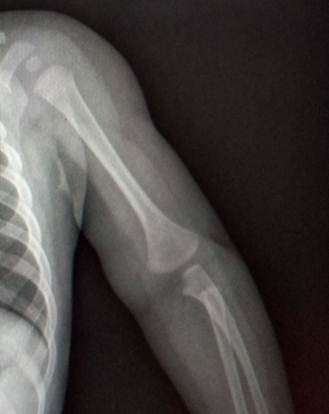

1 год - 3 года

В возрасте года выявляется булавовидный метафиз плечевой кости,

ядро окостенения головчатого возвышения и латерального вала блока.

Верхний конец лучевой кости отстоит от уровня щели локтевого сустава

достаточно далеко. Конец локтевой кости находится на уровне суставной щели. К 3

годам на снимках очерчивается основание головки лучевой кости и хорошо видна

блоковидная вырезка локтевой кости с основаниями локтевого и венечного

отростков. В самом конце периода появляется ядро окостенения головки лучевой

кости.

Прямой снимок локтевого сустава ребенка 5 месяцев. Обратите

внимание, насколько далеко отстоят друг от друга видимые,

т.е. окостеневшие части сочленяющихся костей.

Снимок локтевого сустава ребенка в возрасте 1 года. Заметно ядро

окостенения головчатого возвышения и латерального вала блока плечевой кости.

Ребенок в возрасте 2 лет. Ядро окостенения головчатого возвышения

увеличилось и стало шире. На метафизарной зоне можно увидеть небольшую плоскую

площадку – зону медиального надмыщелка.

Возраст 3 года. Появилось адро окостенения головки лучевой кости.

Площадка медиального надмыщелка отчетливо контурируется.